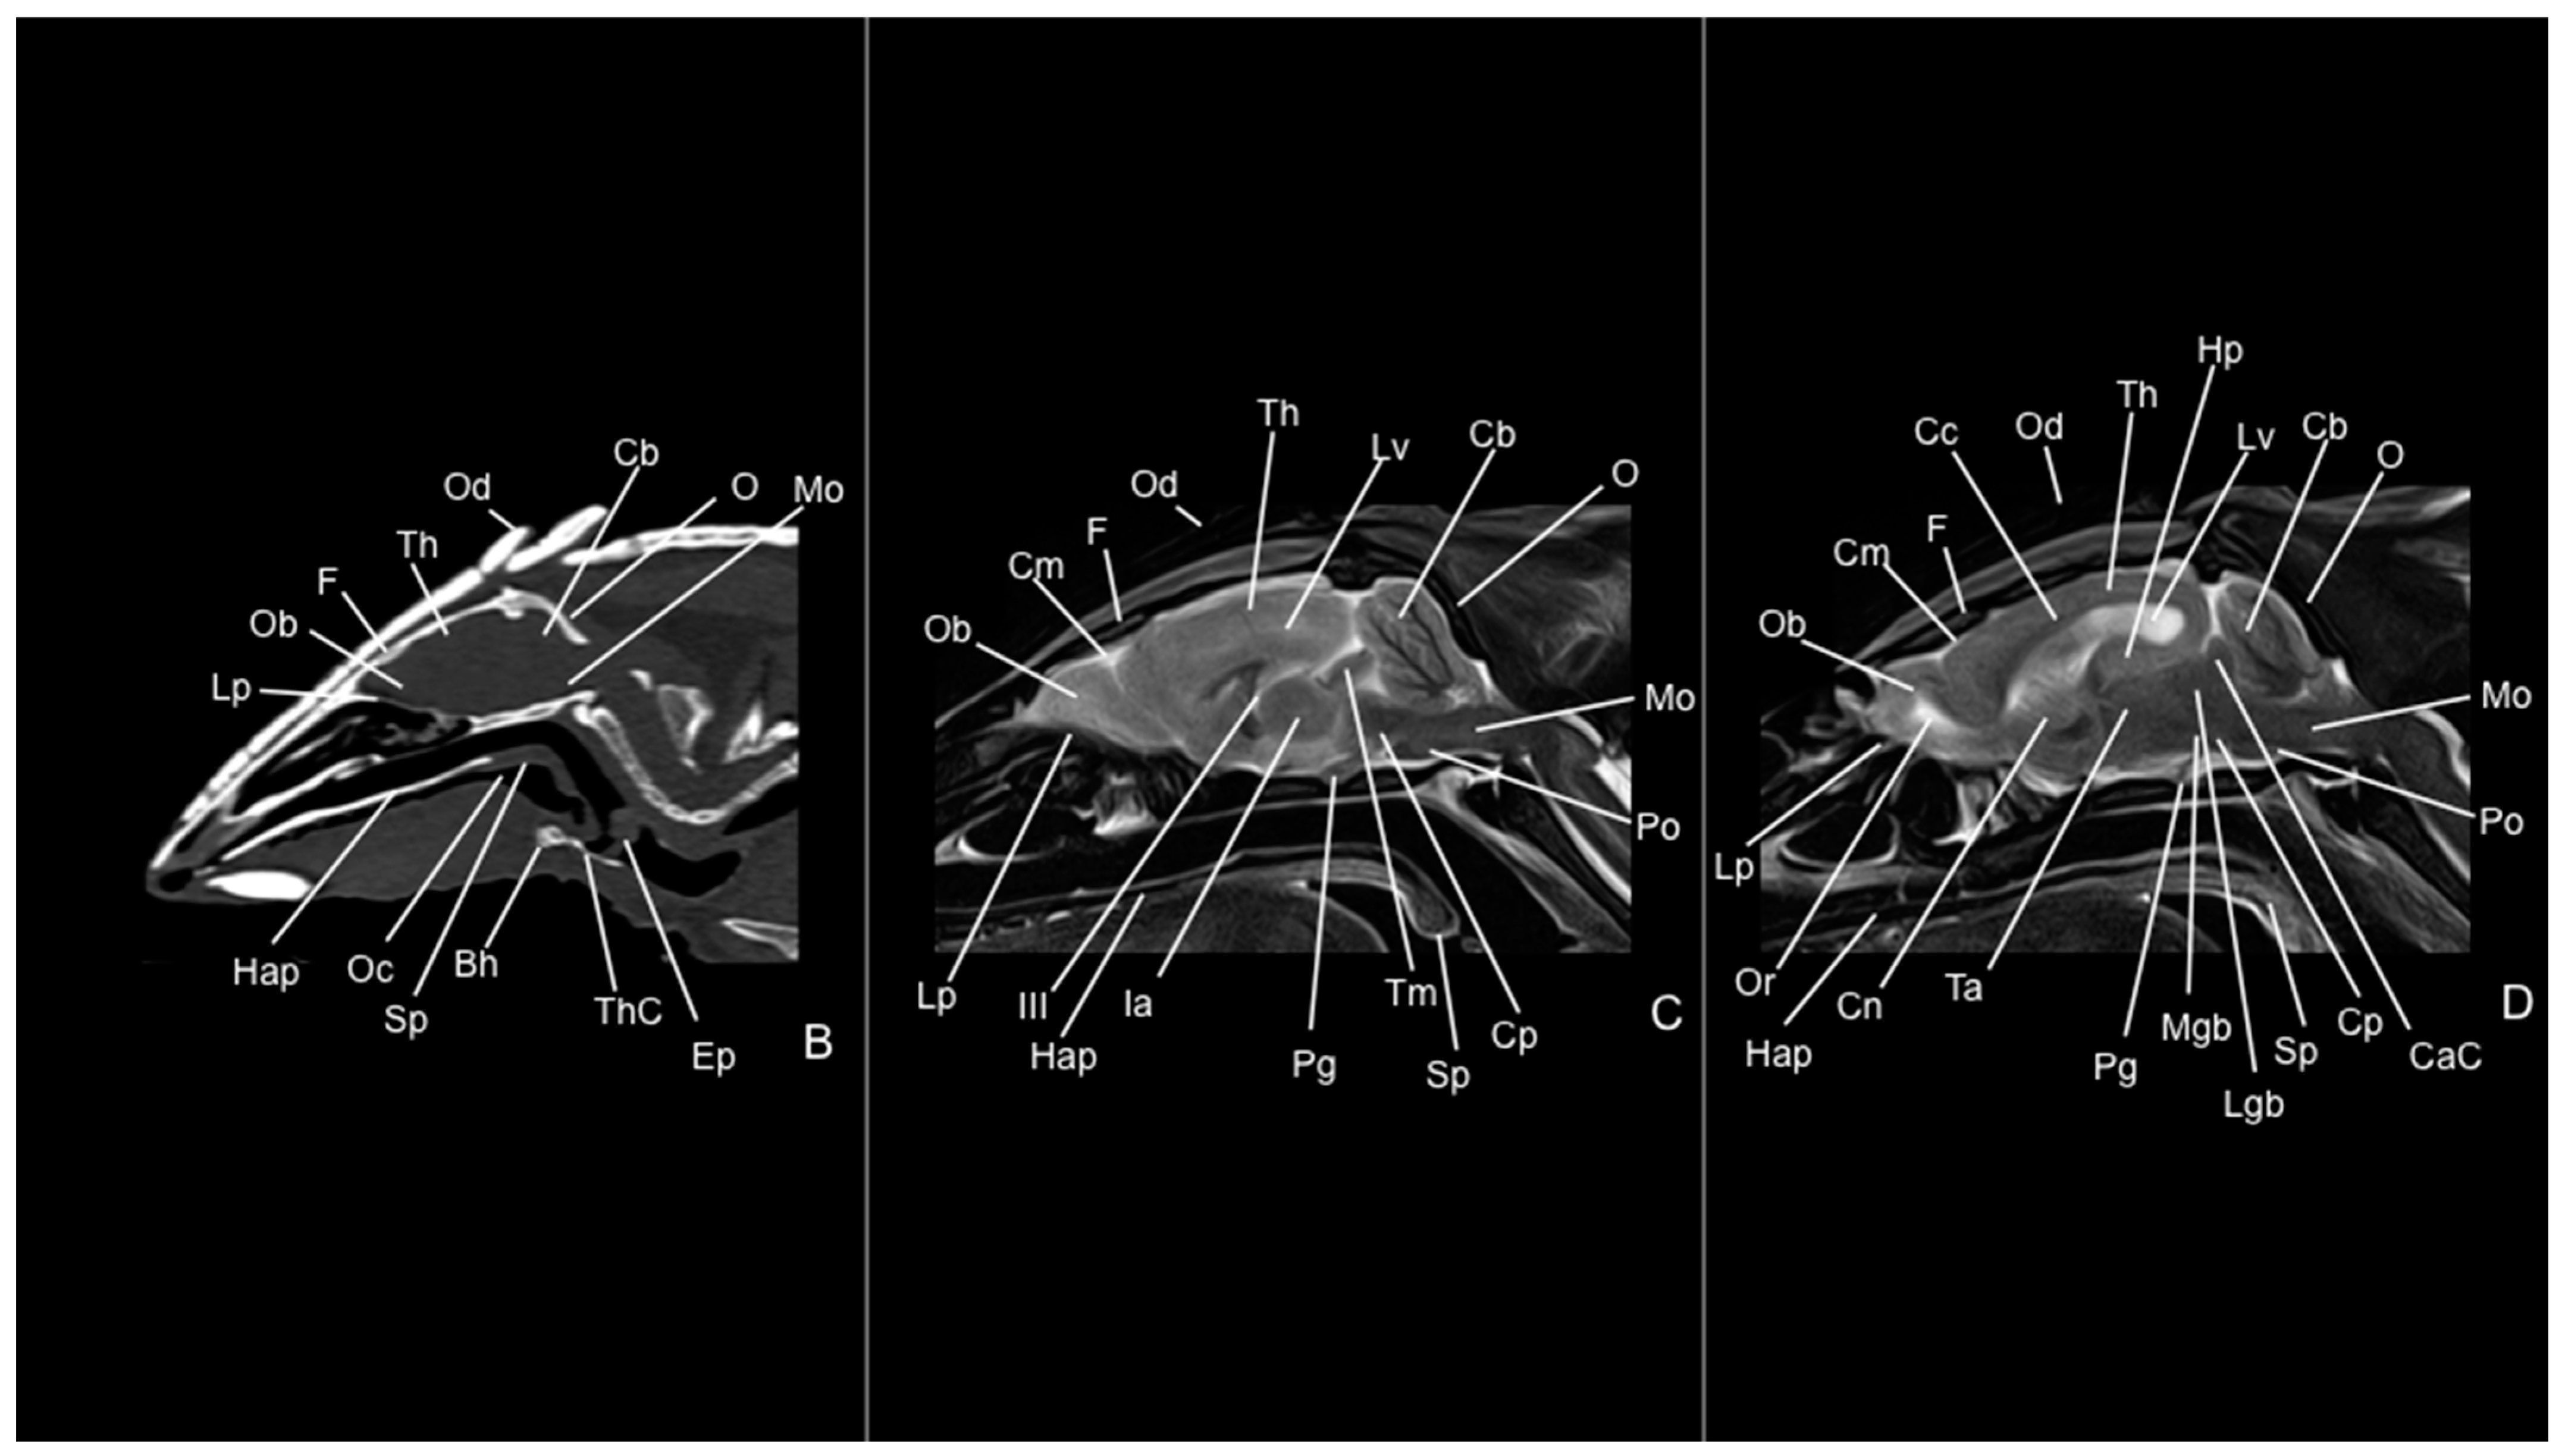

3.1. Anatomical Study

3.2. Computed Tomography Study

3.3. Magnetic Resonance Imaging (MRI)